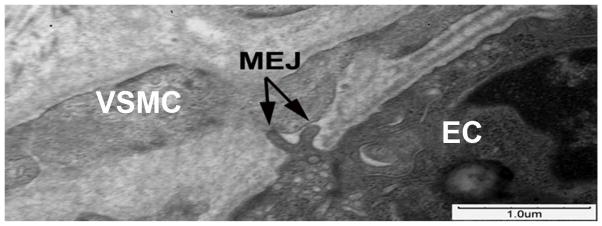

Based on the above data, that MEJs may have a functional role in tumescence, we sought to determine if they were present in human corporal tissue. TEM of human corporal tissue indeed revealed MEJs with the characteristic EC extension penetrating through the IEL to contact the VSMC (Figure 3).

Figure 3. MEJs in human corporal tissue.

Ultrastructural TEM images of human corporal tissue reveals the presence of an MEJ (arrow) between a corporal EC and VSMC.

While MEJs have been reported in the resistance vasculature, they have not been reported in the corpus cavernosum of either the mouse or human; thus, initial studies were simply to identify if MEJs are present in the corpus cavernosum. The presence of MEJs in both the mouse and human corporal tissue indicates that MEJs are not only in the resistance vasculature but also within the venous lacunae of the corporal bodies and suggests they may be important for efficient communication between corporal EC and VSMCs (Figures 1 and 3).